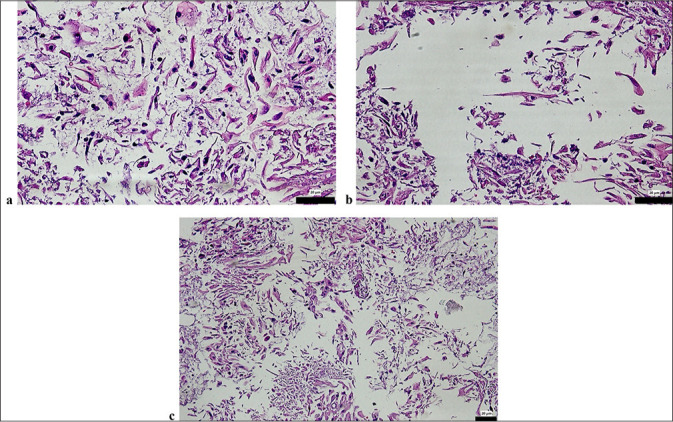

Material and methods: A retrospective analysis was conducted on 60 HPV-positive cervical smear samples processed through the ThinPrep Pap test. CBs were prepared from liquid-based residues, stained with hematoxylin and eosin, and analyzed. Cytological diagnoses were compared with histopathological findings from colposcopy-guided biopsies. The relationships between the Pap smear, CB, and biopsy results were statistically analyzed.

Results: Pap smear cytology identified 1.6%, 16.6%, 43.3%, and 3.3% as high-grade squamous intraepithelial lesion (HSIL), low-grade squamous intraepithelial lesion (LSIL), atypical squamous cells of undetermined significance, and atypical squamous cells - HSIL cannot be excluded + LSIL, respectively. The CB evaluations classified 6.6% of the samples as cervical intraepithelial neoplasia (CIN)1, 1.6% as CIN2, and 1.6% as squamous cell carcinoma (SCC), with 78.3% deemed negative. Histopathological biopsy revealed CIN1 in 11.7%, CIN2 in 1.7%, and CIN3 in 8.3% of the patients. High concordance was observed between the Pap smear and CB diagnoses for negative and low-grade lesions, although discrepancies occurred in higher-grade lesions. HPV testing revealed 65% high-risk positivity, predominantly for HPV16 and HPV18. Significant correlations were found among HPV subtype positivity, CB, and biopsy diagnosis (P < 0.05).